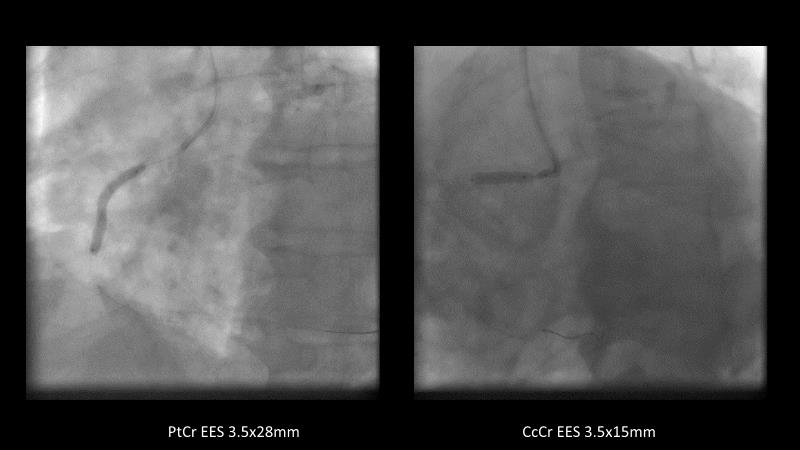

Maximize patient clinical outcomes in complex percutaneous coronary interventions (PCIs) by joining this session. Discover how accurate patient evaluation, advanced imaging/functional modalities, optimized procedures, and the Cre8 EVO device contribute to improved safety and efficacy, and review the challenges associated with DES implantation in complex PCIs.

- To understand how the Cre8 EVO unique technology and its specific design may contribute to improve the procedural success and clinical outcome of complex PCIs in complex patients